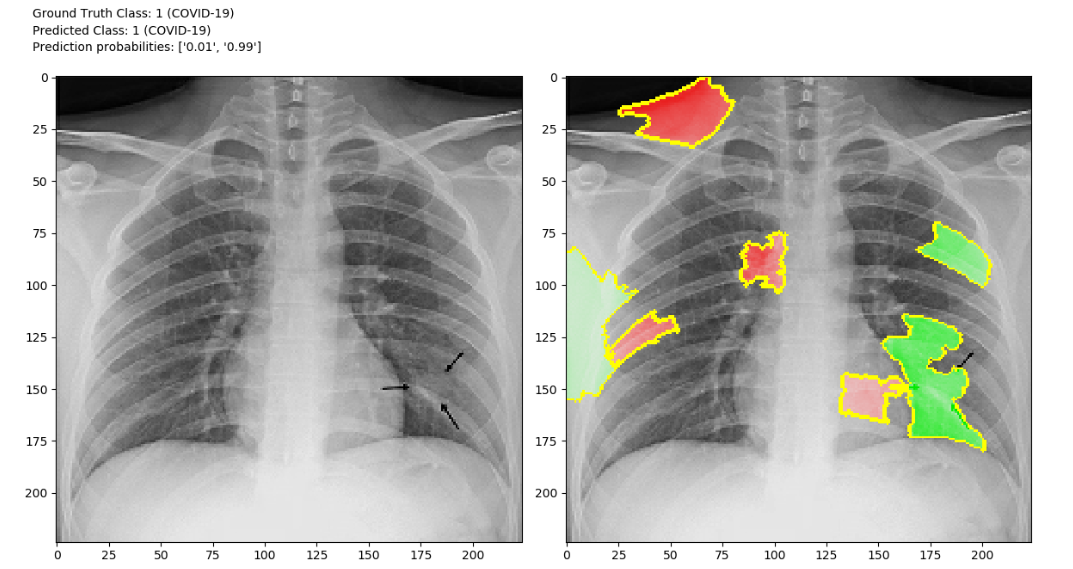

We've built a deep convolutional neural network that classifies the presence of severe COVID-19 in chest X-rays and explains why it made the prediction. This system supports both binary and multi-class classification. Further, the model infrastructure we have open sourced is extensible, modular and well documented, which will allow other researchers to iterate quickly by building on this library.

We first considered a binary classification problem where the goal was to detect whether an X-ray shows evidence of COVID-19 infection. The classifier was to assign X-ray images to either a non-COVID-19 class or a COVID-19 class. A deep convolutional neural network architecture was trained to perform binary classification. The model was trained using the Adam optimizer and categorical cross-entropy loss. All training code was written using TensorFlow 2.0. After numerous iterations, we arrived at a deep convolutional neural network architecture that employs residual connections. Due to the immediacy of the COVID-19 threat, an exhaustive hyperparameter search will be conducted in the future. We applied multiple strategies to combat overfitting, such as L2 weight regularization, dropout regularization and data augmentation (rotation of training set images by up to 10°). We utilized the local interpretable model-agnostic explanations (LIME) algorithm to explain the model’s predictions, which is essential for a model such as this to be adopted in a health care setting.

There are several initiatives that attempt to classify chest x-rays to detect the presence of severe cases of COVID-19. Few of those implementations provide explainable/interpretable AI algoritms. It is imperative that this model be interpretable. Deep convolutional neural networks are not inherently interpretable; rather, they are considered to be “black boxes”. According to an international statement on the ethics of artificial intelligence in radiology, “transparency, interpretability, and explainability are necessary to build patient and provider trust”. Clinicians are not likely to put all their trust in the predictions of a black box algorithm, nor should they. By providing explanations for why our model predicts COVID-19 infection or lack thereof, any researchers or clinicians interested in improving this system may gain an appreciation of why the model makes a particular decision. Not only is it ethically responsible to pursue explainable machine learning models, it is also informative to researchers to ensure that there is no data leakage or unintended bias in the model. We are glad that we explored explainability methods, as we noticed multiple sources of possible data leakage in our model and in the approaches of others in the data science community.